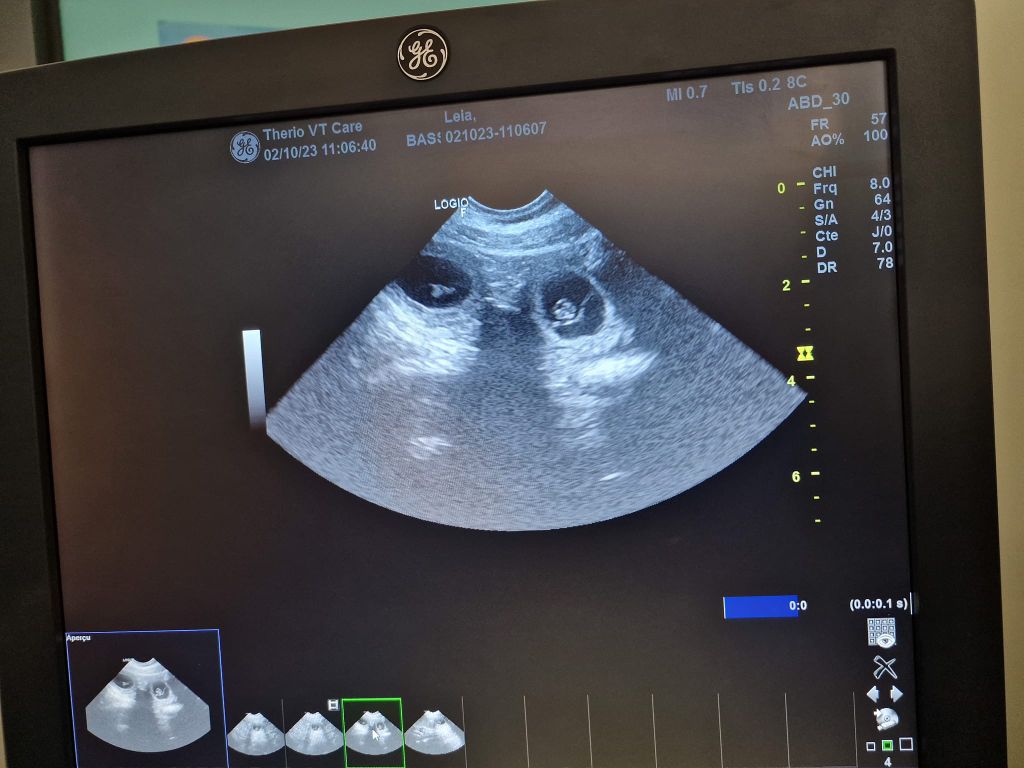

Gestation Leia Confirmation de gestation à J+23 les petits precious 5eme semaine maman pète la forme J-13 la nurserie est prête J-13 la nurserie est prête J-13 la nurserie est prête 6eme semaine le bidou pousse bien